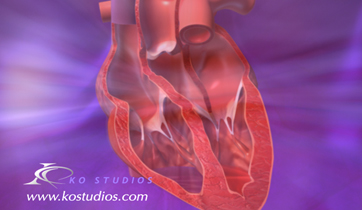

Diastolic Cardiac Insufficiency

Sanofi

ScienceProd, Paris

The Angiotensin - Aldosterone - Renin system is triggered by the thickening of the left ventricle and improper filling of the venticular chamber. This triggers the release of aldosterone, noradrenaline, and angiotensin II which binds to fibroblasts, releasing collagen and increasing myofibril rigidity.

Natracor; hBNP MOA

Scios Pharmaceuticals

Adair Greene Advertising

Natracor treats congestive heart failure triggered by the renin - angiotensin - aldosterone system which causes sodium and fluid retention and vaso-constriction. hBNP is a regulatory hormone, which binds to Guanylate cyclase receptors to reverse effects.

Eisenmenger Syndrome

Actelion Pharmaceuticals, Ltd.

ScienceProd, Paris

Eisenmenger syndrome is caused by a hole in the septum between the left and right ventricles of a baby's heart (ventricular septal defect). The hole allows oxygenated blood to flow back into the lungs, instead of going out to the rest of the body.